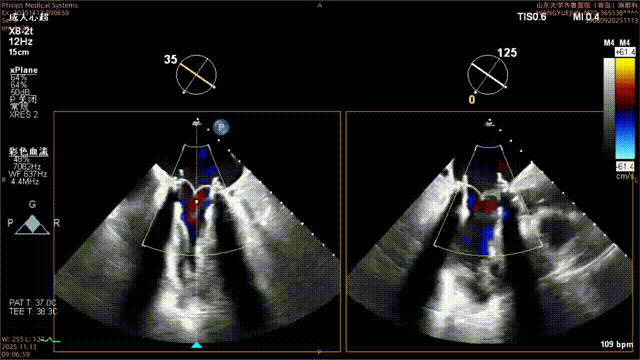

超声提示:

二尖瓣生物瓣置换术后

二尖瓣生物瓣退行性病变狭窄(重度)并反流(轻-中度)

二尖瓣瓣架前缘中等回声(残存腱索可能性大)

左房扩大

三尖瓣反流(轻度)

肺动脉瓣反流(轻度)

肺动脉高压(轻度)

术中影像

二尖瓣打开通畅,无瓣周漏

二尖瓣

最大流速:104cm/s

平均压差:术前21mmHg→ 术后2mmHg

无需进行球囊后扩张